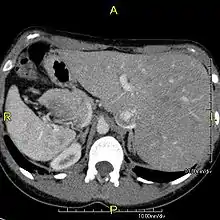

Diagnosis of situs inversus can be made using imaging techniques such as x-ray, ultrasound, CT scan, and magnetic resonance imaging (MRI).[7]

The condition affects all major structures within the thorax and abdomen. Generally, the organs are simply transposed through the sagittal plane. The heart is located on the right side of the thorax, the stomach and spleen on the right side of the abdomen and the liver and gall bladder on the left side. The heart's normal right atrium occurs on the left, and the left atrium is on the right. The lung anatomy is reversed and the left lung has three lobes while the right lung has two lobes. The intestines and other internal structures are also reversed from the normal, and the blood vessels, nerves, and lymphatics are also transposed.